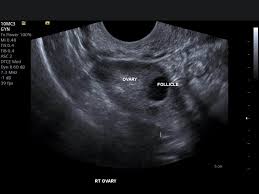

During an abdominal ultrasound, a small handheld device called a transducer is gently moved across the skin of the abdomen. The transducer emits high-frequency sound waves that penetrate through the abdominal tissues and bounce off the organs and structures inside. These sound waves are then converted into real-time images on a monitor, allowing the healthcare provider to examine the internal organs and identify any abnormalities.

Abdominal ultrasound can provide detailed images of several organs within the abdomen, including the liver, gallbladder, pancreas, spleen, kidneys, and abdominal aorta. It can also visualize the surrounding structures such as blood vessels, lymph nodes, and abdominal wall.